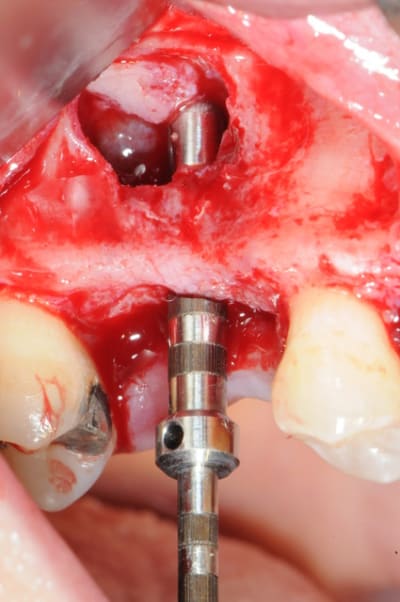

le sujet tombe à pic!

je viens de faire un sinus lift ce matin;

- 3 à 4 mm de hauteur sous sinusienne

- des cloisons de refend partout

- comblement avec du Vital Os

- un implant Axiom D4 L 10

comme je n'avais pas le temps de faire des photos la dernière fois et que j'en étais frustré, je me suis un peu lâcher aujourd'hui...

les premières photos, c'était ouverture par voie latérale

les suivantes;

- forage et transperçage de la crête sans aller trop loin...

- essayage pilier pour parallélisme

- forage à 3mm

- visualisation de la hauteur sous la membrane de Schneider

- utilisation d'un ostéotome diamètre 3.4 puis 3.8

(sous dimensionnement de diamètre par rapport à l'implant prévu :4mm)